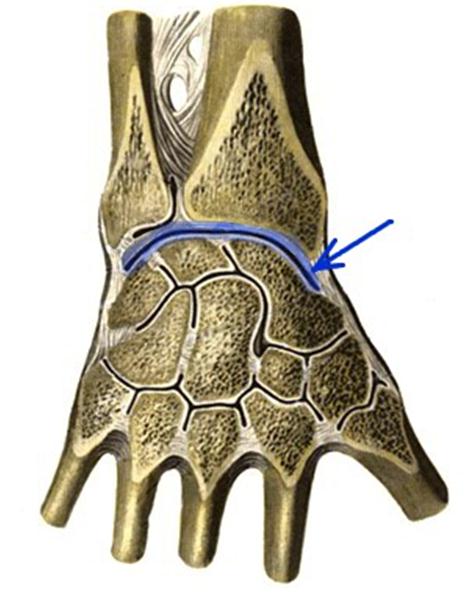

S: Стрелка указывает на art....

-:carpometacarpea

+:radiocarpea

-:radioulnaris distalis

-:mediacarpea

-:intercarpea